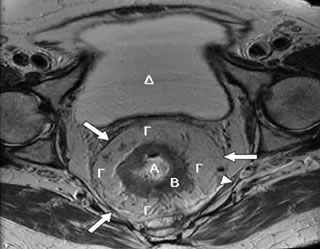

- Η μαγνητική τομογραφία πυέλου αποτελεί βασικό μέσο προεγχειρητικής σταδιοποίησης του καρκίνου του ορθού (εκτίμηση του βάθους διήθησης του όγκου εντός του μεσοορθού, απόσταση του όγκου από την ιδίως μεσοορθική περιτονία, παρουσία λεμφαδενικών μεταστάσεων ή καρκινικών εναποθέσεων εντός του μεσοορθού) (Εικόνα 11).

Εικόνα 11.

Μαγνητική τομογραφία πυέλου:

Α. Αυλός ορθού. Β. Μυϊκός χιτώνας ορθού. Γ. Μεσοορθικό λίπος (το μεσοορθό περιβάλλει το ορθό κυκλοτερώς, οπισθίως, πλαγίως και προσθίως). Δ. Ουροδόχος κύστη. (Μεγάλο βέλος: Μεσοορθική περιτονία. Μικρό βέλος: Μεσοορθικός λεμφαδένας)

- Το διορθικό υπερηχογράφημα έχει ένδειξη στη σταδιοποίηση του επιπέδου Τ του καρκίνου του ορθού (εκτίμηση βάθους διήθησης του όγκου διά των εντερικών στιβάδων) και του Ν (ανίχνευση αυξημένου μεγέθους μεσοορθικών λεμφαδένων με υπερηχολογικά χαρακτηριστικά ενδεικτικά μετάστασης).